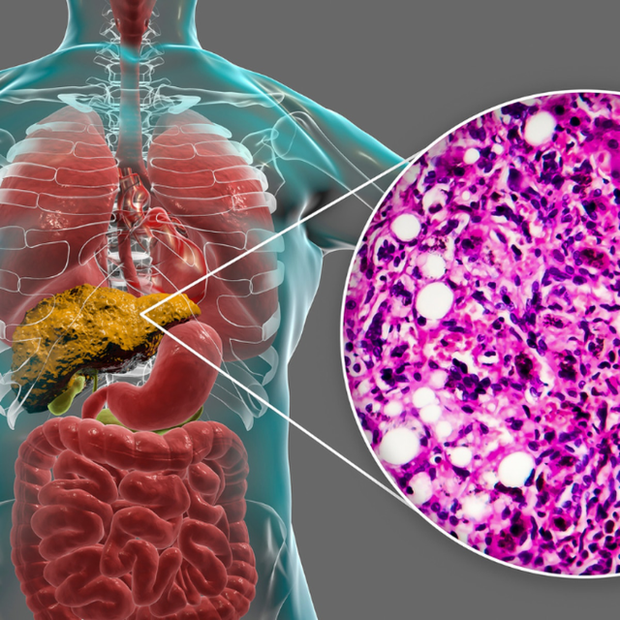

Mô phỏng tình trạng gan nhiễm mỡ (Ảnh: Getty)